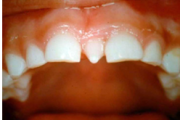

Koonilise kujuga lisahammas ülemiste tsentraalsete lõikehammaste vahel.

Suulaepoolt lõikunud koonilise kujuga lisahammas